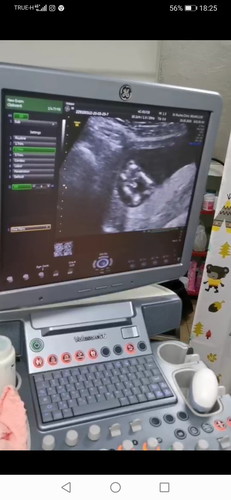

ตอนนี้14w1dค่ะ ไปซาวด์มา แม่ๆคิดว่าเพศอะไรคะ ?